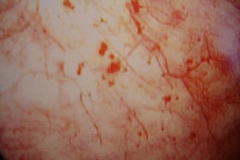

膀胱炎诱因有结石、异物、肿瘤或阻塞性病变,包括由于神经系统疾产生的排尿功能障碍等。膀胱炎的急性炎症的病理变化有粘膜充血、水肿、出血和溃疡形成,并有脓液或坏死组织。慢性炎症主要有粘膜增生或萎缩、肉芽组织形成,并有纤维组织增生,膀胱容量减少;或并发阻塞所引起的肌肉肥大,膀胱容量增大甚至有憩室形成等改变。还有一种特殊的炎症变化是坏疽性膀胱炎,为梭形杆菌、产气荚膜杆菌等引起的严重膀胱炎症。